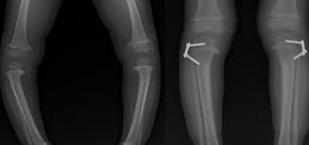

مالك يعاني من قصر بعضلات السمانة

الطفل مالك 6 سنوات يعيش مع اب وأم في منطقة شعبية، الأسرة محدودة الدخل، تسعى جاهدة لتأمين علاج ابنيهما قبل ...

تقوص الركب يمنع هاجر من العودة للمدرسة

الام ايمان تروي دامعة العين على طفلتها هاجر التي تعاني من تقوص في الركب نتيجة لنقص الكالسيوم جراء سوء التغذية ...